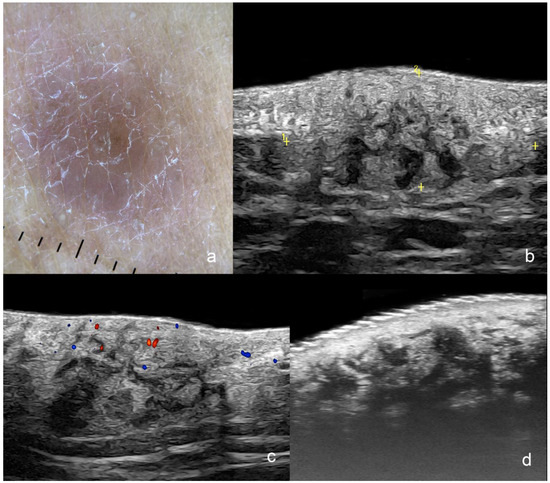

1.3.2. Squamous Cell Carcinoma (SCC)

Primary SCC Tumor

| Squamous Cell Carcinoma | hypoechoic, crumpled, wavy or irregular epidermis, convex, concave flat, bulging or fusiform shape, irregular borders | intermediate degree |